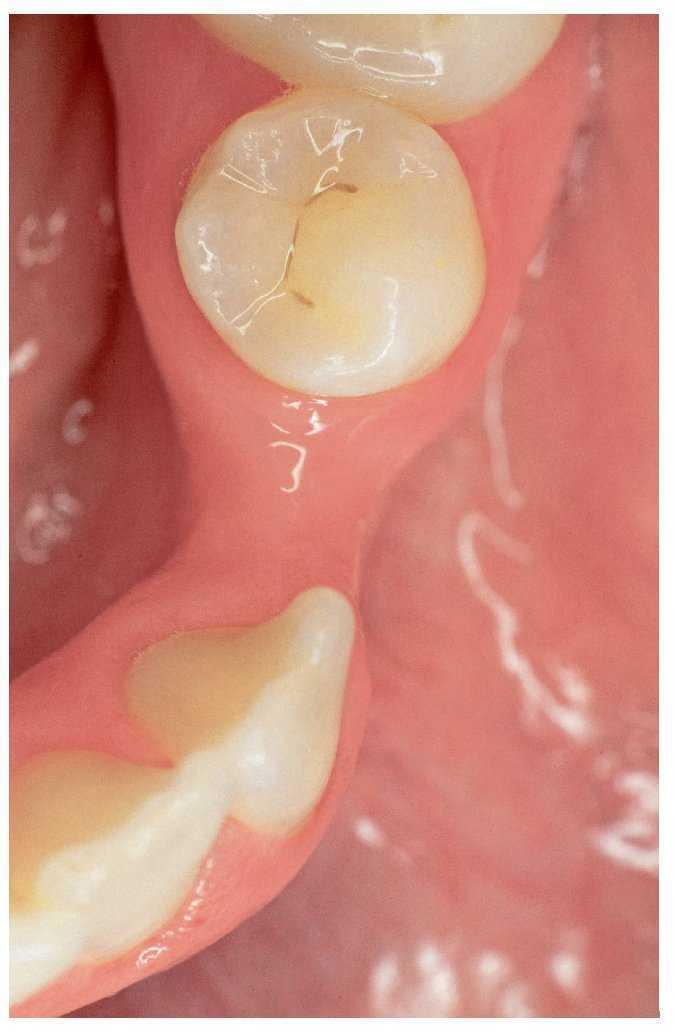

Figura 4a. Ausencia del diente 36, diente 35 sin caries y obturación oclusal en el diente 37.

Figura 4b. Puente adhesivo de metal cerámica de doble aleta que incluye la obturación oclusal.